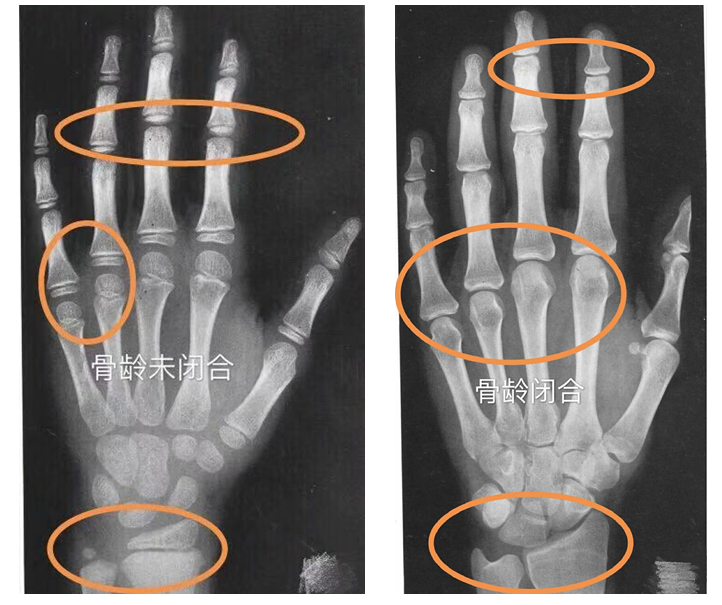

骨骺闭合,身高不再长

人的身高增长是有时限的,临床医学表明,一般情况下,人的骨骺在14-15岁的时候就会闭合,一旦骨骺闭合,无论任何方法,都不可能再长高。什么是骨龄?骨龄是骨骼年龄的简称。借助于骨骼在x光摄影中的特定图像来确定,骨龄能够较为准确反映人体的生长发育状况和身高增长空间,骨龄一旦成熟身高也失去了线性增长的机会,因此骨龄是临床诊疗矮身材必须要做的检查项目之一。